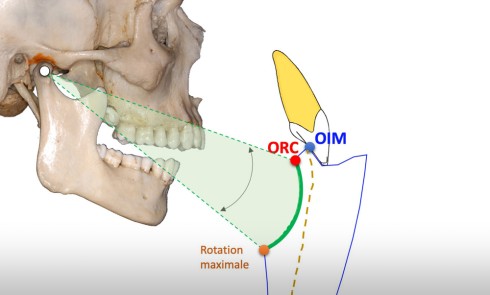

Un patient allongé avec la tête en hyperextension n’aura probablement pas les mêmes contacts occlusaux qu’en position assise, tête droite, jambes décroisées. Il est donc préférable de relever le patient avant d’effectuer un contrôle visuel de l’occlusion (fig. 1).